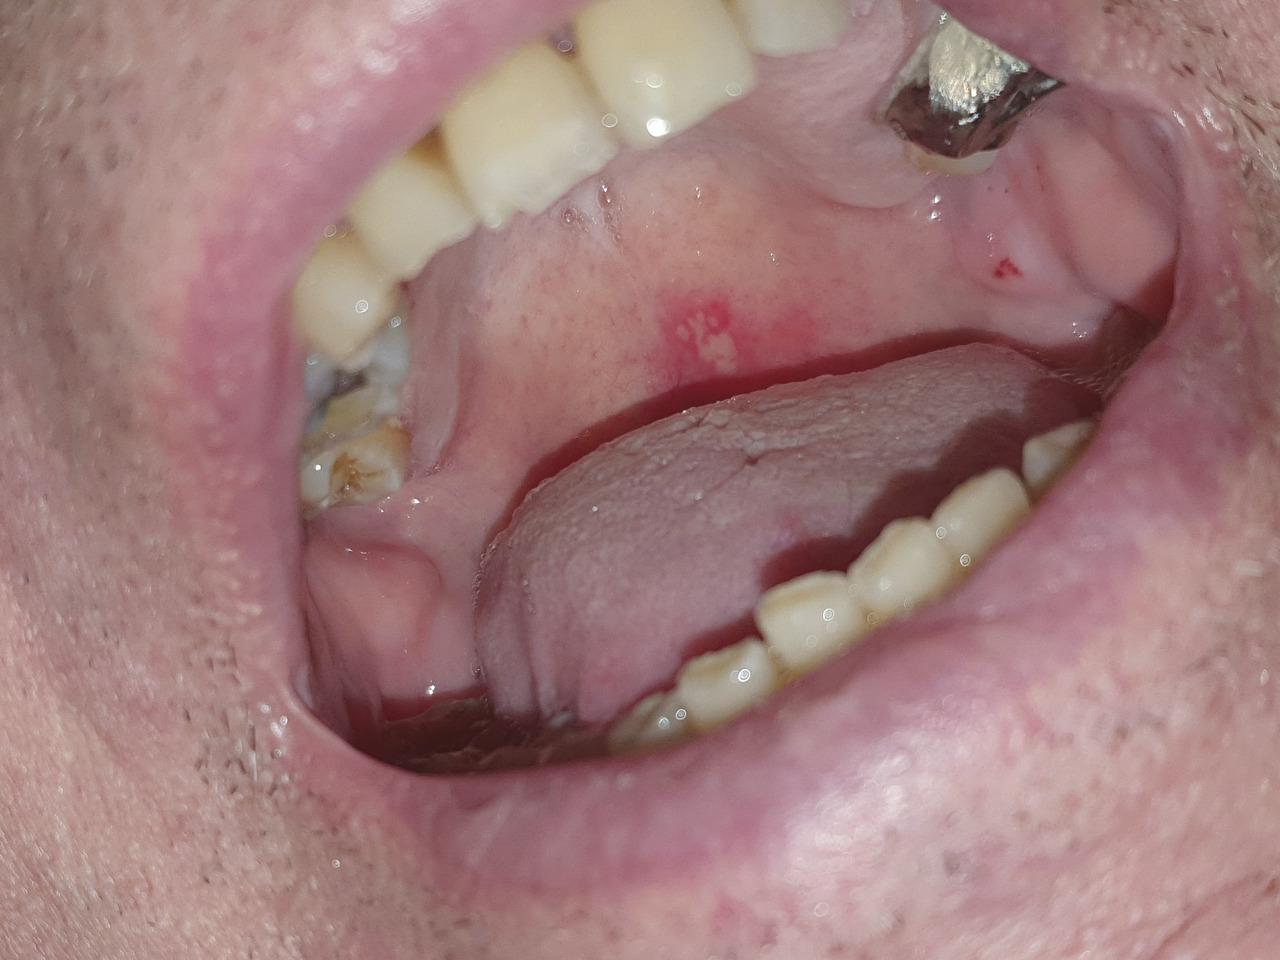

Sylvain, 53 ans, consulte pour douleurs oropharyngées importantes, apparues cinq jours plus tôt, après un traitement par corticoïdes pour une angine virale prescrit par un confrère. Il a très fréquemment, depuis son adolescence, des « boutons de fièvre » et des douleurs buccales. L’examen clinique met en évidence un bouquet de vésicules au niveau du palais (photo ).

La récurrence oropharyngée se caractérise par l’apparition de lésions vésiculeuses parfois pustuleuses, en bouquet, avec pharyngite, voire laryngite ou œsophagite.